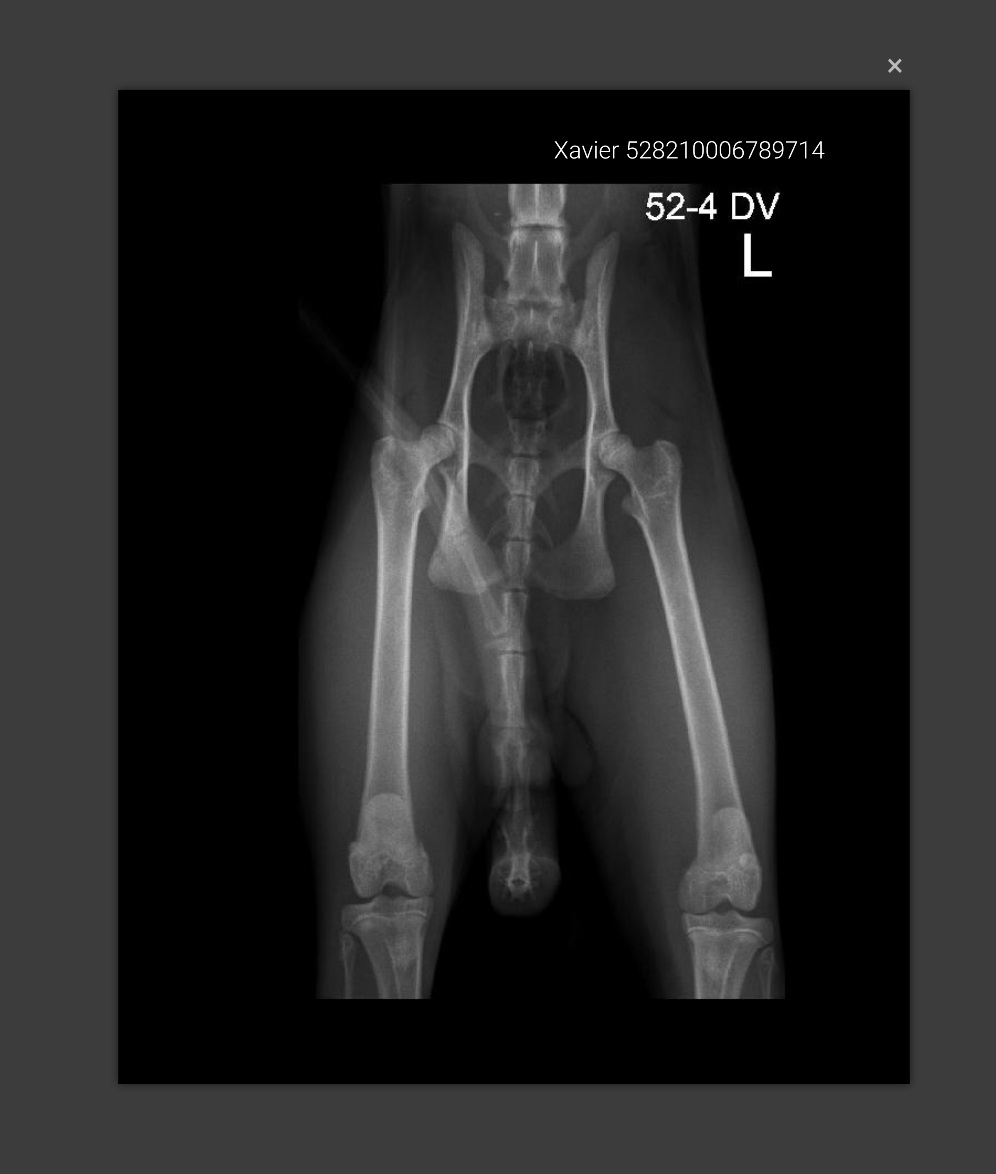

Xavier screen HD heupen 👍

Afbeelding – 82,7 KB

158 downloads

Download